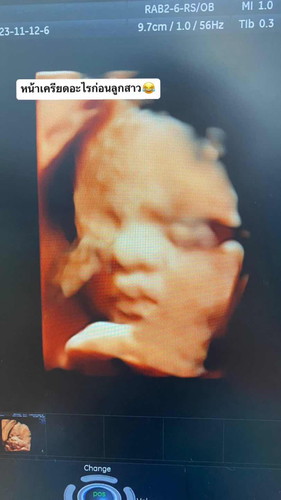

29 w ซาว 3 มิติ

สอบถามแม่ๆหน่อยค่ะ ในรูปน้องปากน้องเป็นกระจับใช่ไหมคะ 😊😊

ใช่ค่ะ ปากกระจับ สวยมากค่ะ

29 w ค่ะ